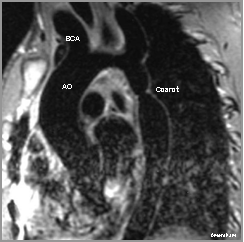

Oblique sagittal spin-echo-Coarctation of the Aorta